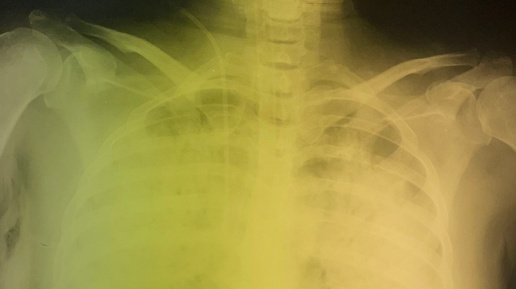

)! 🦠️ «Испанка» — самая смертоносная пандемия XX века, и не без загадок. Поразительно, но, в отличие от обычного гриппа, который уносит, в основном, пожилых и детей, тогда часто умирали молодые, сильные люди. Почему? Виновато редкое, но крайне опасное осложнение: острый респираторный дистресс-синдром, или ОРДС. Что это? ОРДС — катастрофический ответ иммунной системы: очаги воспаления разрушают альвеолы в лёгких, истончая их стенки. Жидкость, белки и даже клетки начинают «просачиваться» в пространство, где должен быть чистый воздух. Врачи описывали лёгкие погибших как «кисель» или «стекло» — они теряли воздушность...